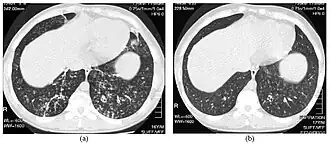

Инфекционный бронхиолит. КТ-скан наддиафрагмальных отделов грудной полости до и после лечения. | |

«Дерево в почках» (англ. Tree-in-bud sign)[1] — радиологический симптом поражения терминальных отделов бронхиального дерева. Представляет собой мелкие центрилобулярные разветвлённые Y- или V-образные структуры толщиной до 1-2 мм с утолщениями на концах.

Морфологическим субстратом этих центрилобулярных узелков является утолщение стенок бронхиол и заполнение их расширенного просвета слизью или гноем (что позволяет визуализировать эти невидимые в норме анатомические структуры). Данная КТ-картина может выявляться как при эндобронхиальном распространении инфекционного процесса, так и при неинфекционных заболеваниях (силикоз, антракоз).